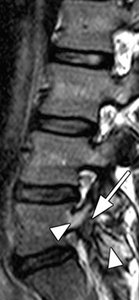

FIG 3 Magnetic resonance sagittal slice through the lumbar spine demonstrates stress fracture at the pars interarticularis of L5. Note marrow edema (bright signal arrows), fracture line arrow with tail.

Another common injury is a stress fracture of the pars interarticularis. Often the stress reaction is not visible on X-rays and even MRI studies can be equivocal. A SPECT bone scan may be necessary to diagnosis spondylolysis. It is a relatively common cause of back pain in young athletes.

In a retrospective study of youth soccer players diagnosed with lumbar spondylolysis, those who took at least three months off from the sport, with or without bracing, experienced the best results. Other studies indicate the average time needed to return to sport is five months.9-10 Figure 3 demonstrates bilateral stress fractures of the pars on MRI. Patient is a 15-year-old male who played basketball.